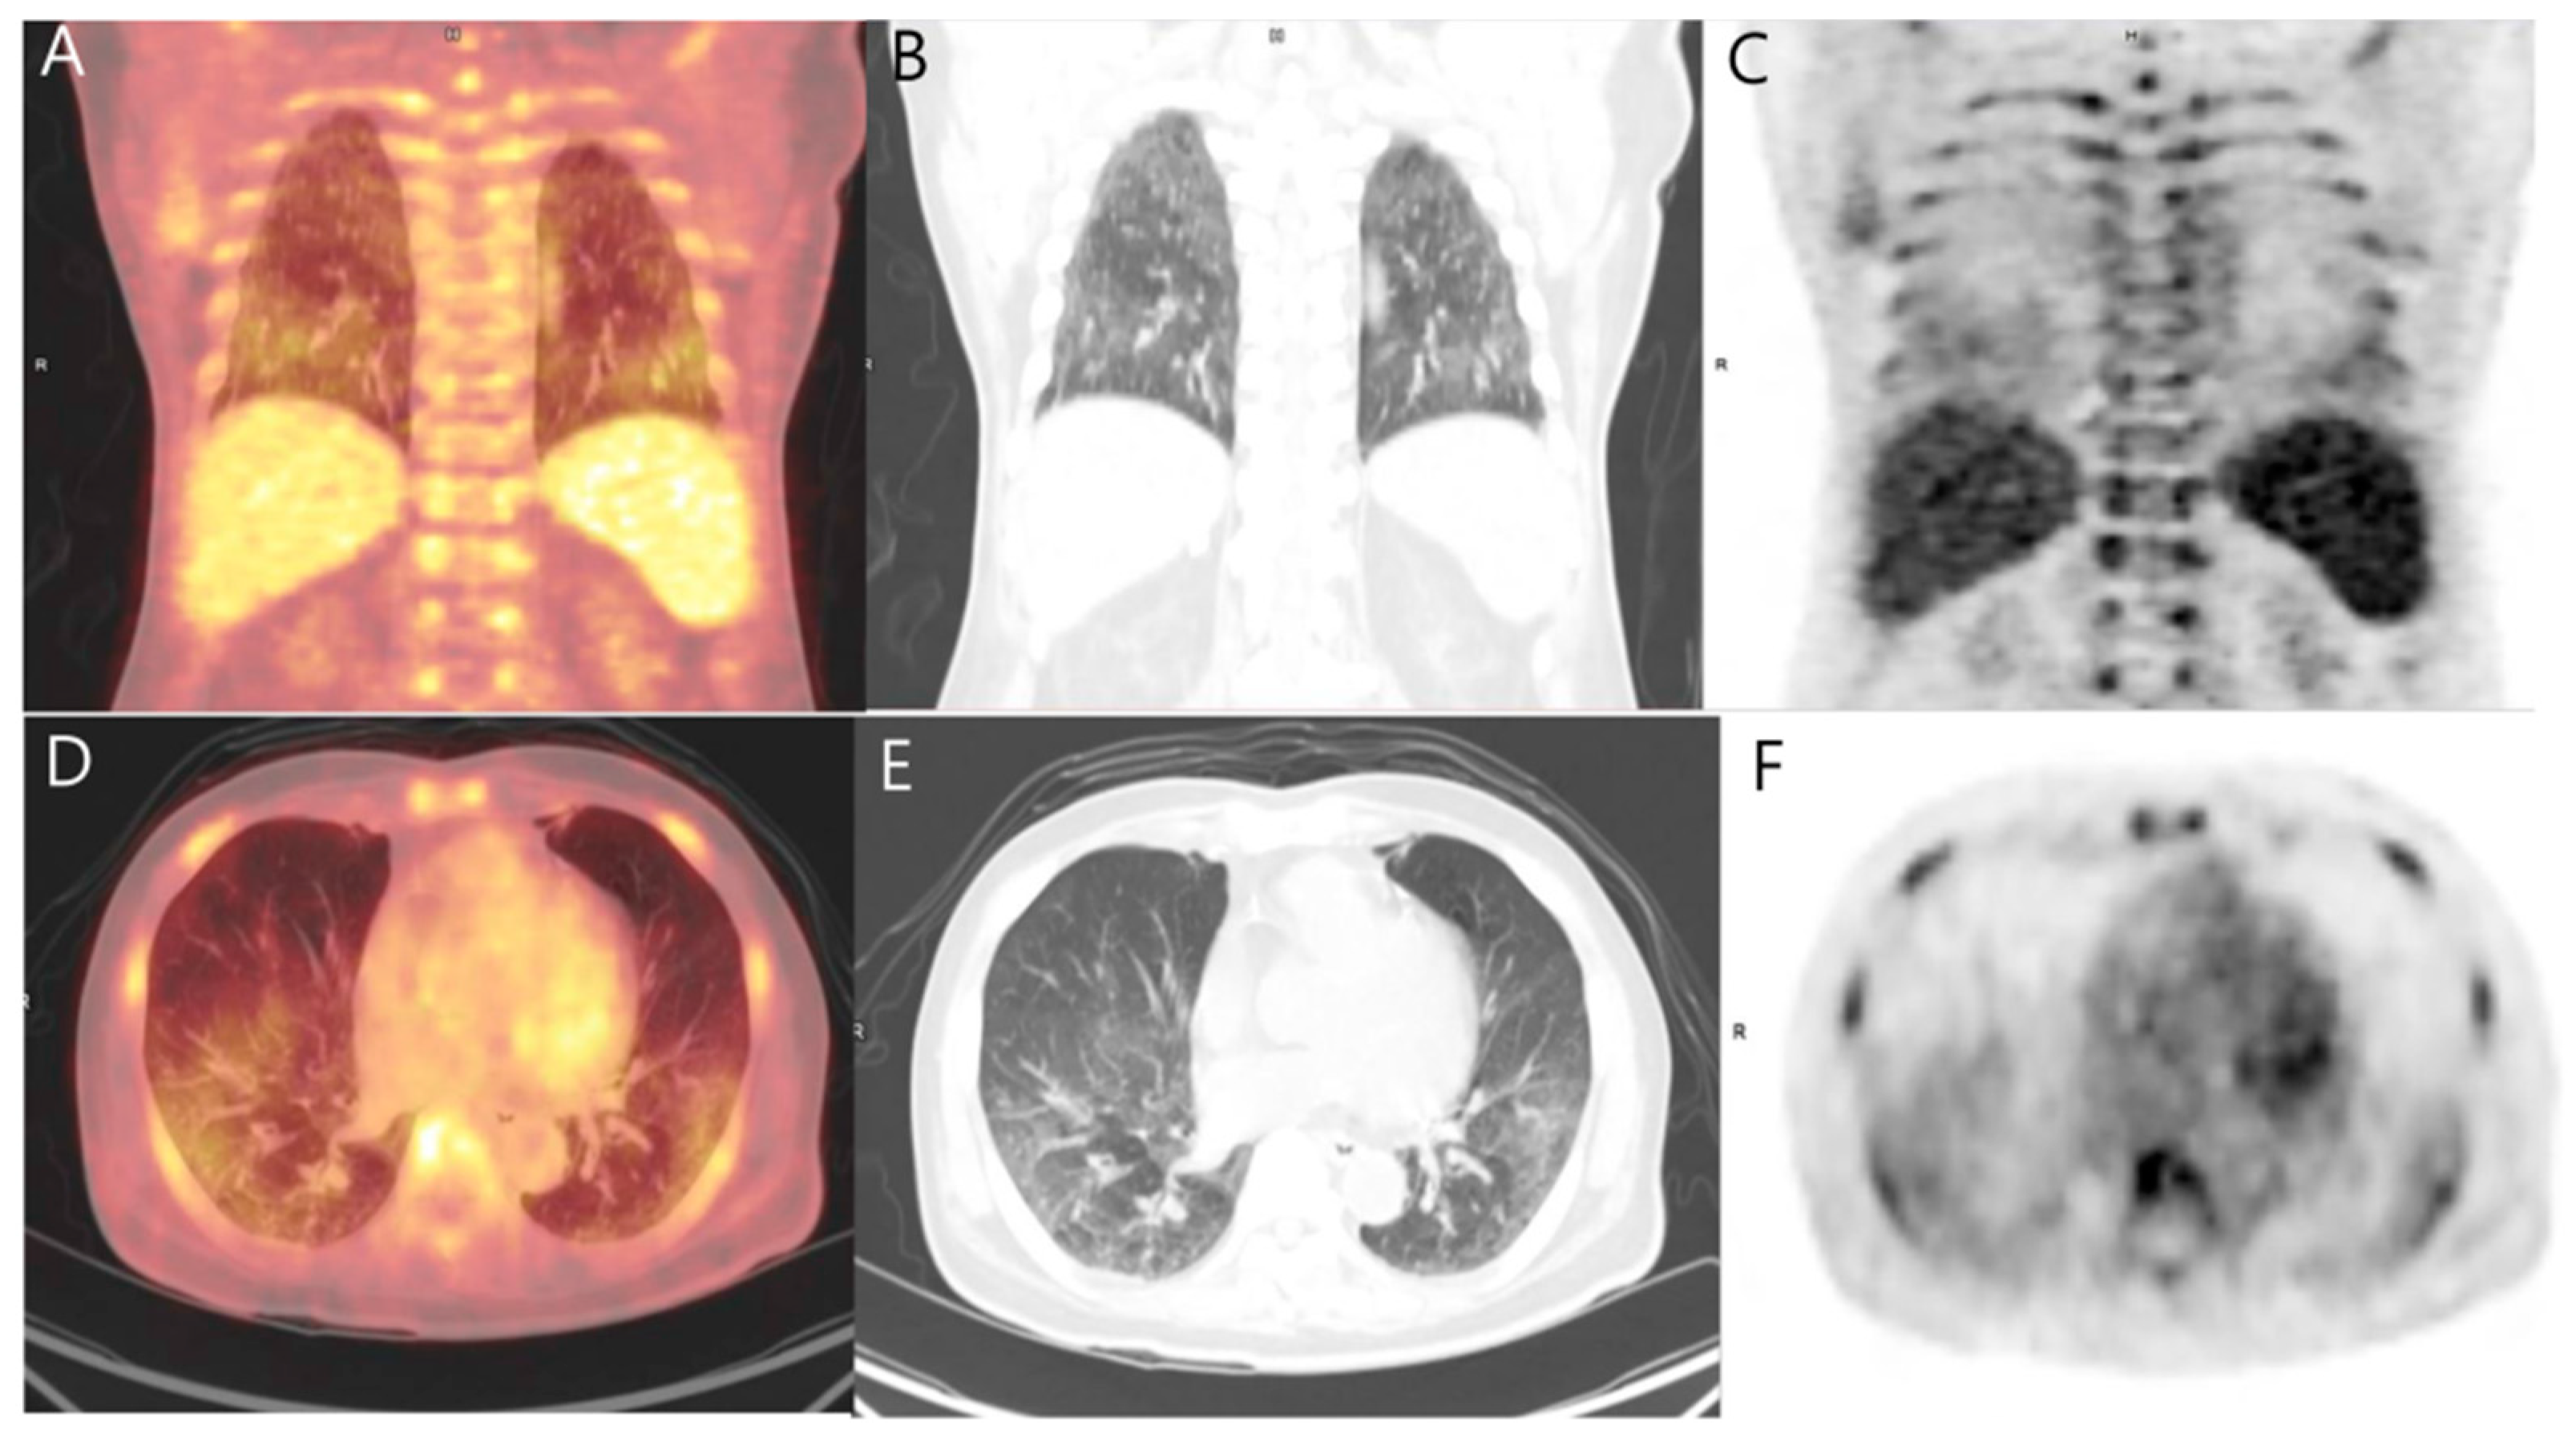

FDG PET/CT [(A) 7/21] with multiple FDG avid bone metastases (ribs Pet Ct Scan For Bone Metastases the detection of bone metastases in patients with high risk. this article compares the effectiveness of the pet/ct scan and bone scintigraphy for the detection of bone. Breast cancer is the most frequent cancer in women and remains the second leading cause of. Pet Ct Scan For Bone Metastases.

From www.mdpi.com

Diagnostics Free FullText Metastatic Pulmonary Calcification Pet Ct Scan For Bone Metastases the detection of bone metastases in patients with high risk. Breast cancer is the most frequent cancer in women and remains the second leading cause of. this article compares the effectiveness of the pet/ct scan and bone scintigraphy for the detection of bone. Pet Ct Scan For Bone Metastases.